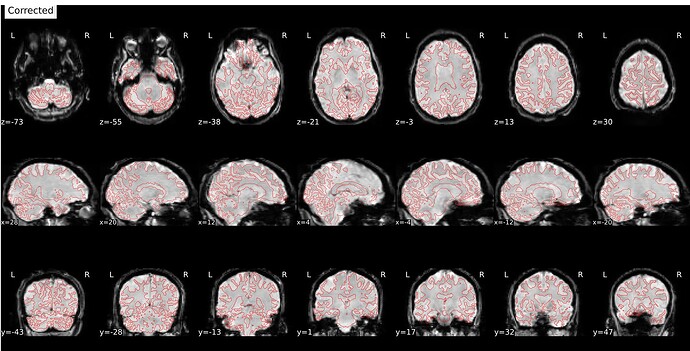

I’m seeing an apparent misalignment in the fmapCoreg reportlet for a PEPOLAR (SE-EPI AP/PA) distortion-correction workflow

- The SDC before/after panel looks okay-ish, suggesting distortion correction itself is likely working somehow, but poor than for subjects where fmap-bold coreg works as expected.